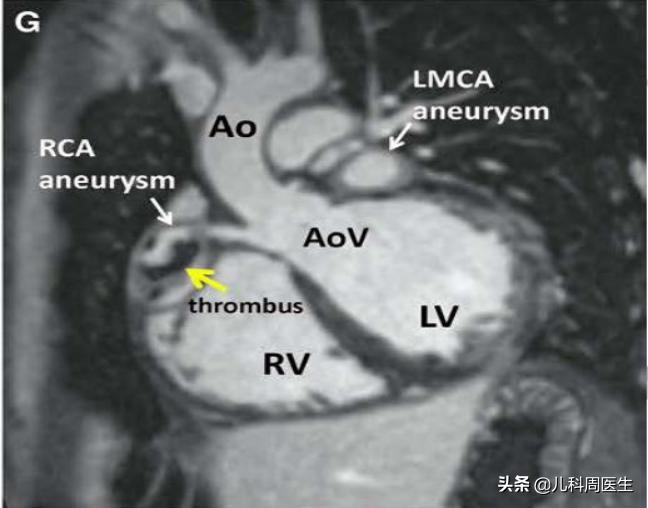

核磁共振显示:白色箭头有冠状动脉瘤